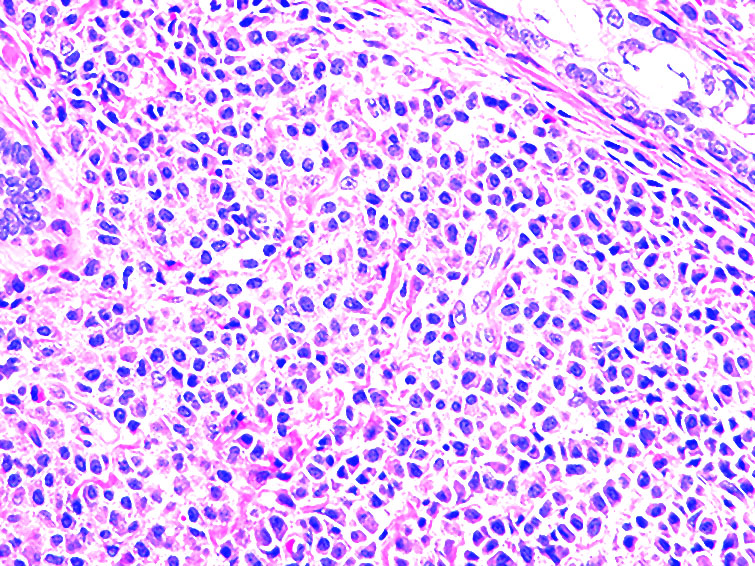

Microscopic (histologic) description

- Within the macules and plaque, mast cells are predominantly in papillary dermis

- Mast cells are round or spindle shaped with abundant eosinophilic cytoplasm, distinct cytoplasmic boundaries, large pale nuclei

- Eosinophils are often present

- Also edema of papillary dermis, subepidermal vesiculation

Microscopic (histologic) images